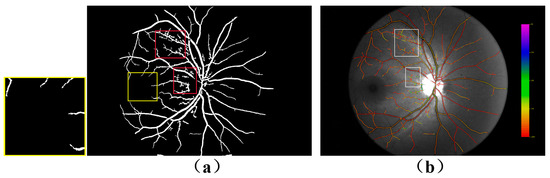

4.1. Comparison of Dual-Wavelength Retinal Image Segmentation Results